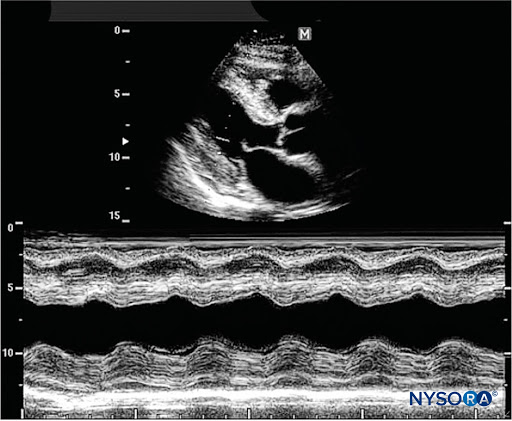

М режим

Цветной М режим

Тканевой М режим

- Кардиология

Кардиология (сердце) в М-режиме |

Помбо, Тейхольц, Гибсон, митральный клапан, LA/Ao, трикуспидальный клапан, клапан легочного ствола, нижняя полая вена IVC, асинхрония CRT (для пациентов с ресинхронизирующей терапией - кардиостимуляторами). |